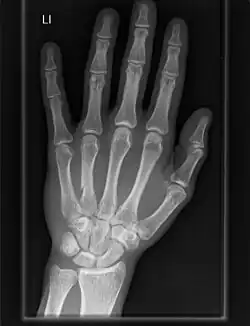

Osteoarthritis of the carpometacarpal joints is a type of joint disease that results from breakdown of joint cartilage and underlying bone.[13] When it affects the thumb it is termed trapeziometacarpal osteoarthritis.

Carpometacarpal bossing is the presence of a small immovable protuberance over the joint.[14]